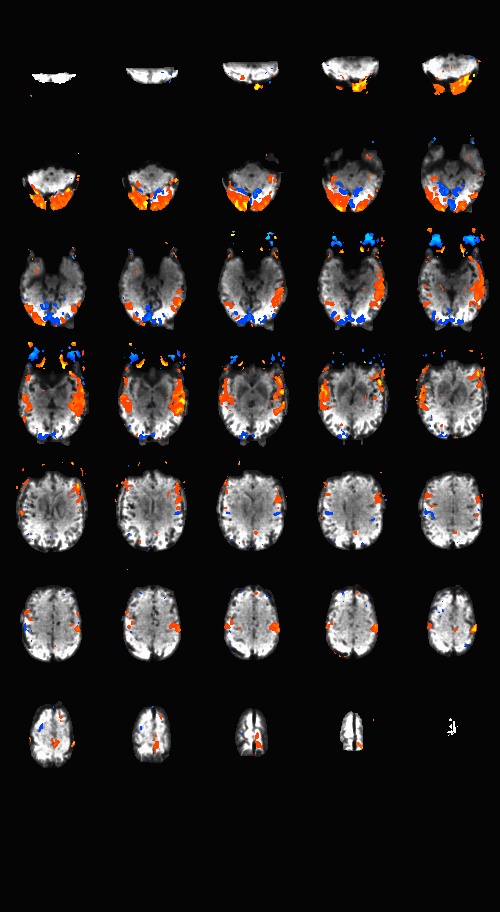

Sequences to UseWhat pulse sequence to use for fMRIThere are a variety of different pulse sequences that can be used for fMRI, including the standard Siemens EPI product sequences; multi-band EPI sequences from MGH and Univ. of Minnesota; and spiral sequences implemented by David Ress.

Here is another analysis of the same data by David Ress. The results are similar, with the G2, MB2 version winning by around 15% in fSNR over the product sequence. But, the shorter TR will also net you an improvement of ~5% in CNR in a similar length run. It is also interesting, however, that the G3 run had less aliasing artifact, suggesting that shorter acquisition times reconstruct more cleanly. Similar results were obtained with a phantom: What T1-weighted Anatomicals to UseMost studies collect at least one scan with structural contrast in order to align their other runs (functional, DTI, etc) to other participants and to published atlases. In some cases, measurements such as volume or cortical thickness are also derived from these scans. We have tested a few of these on the Prisma (Bay 4) and will run similar analyses on the Trio (Bay 5) soon. CAMRI (specifically, Meghan) recommends the following scans for new studies, and can easily set these up in your protocol: (1) 1mm isotropic scan. Acquisition time: 4:01. Contrast to noise ratio (CNR): ~2.0. This is a good choice if speed is of the essence, and your main goals are alignment of lower-resolution scans. (2) 1mm isotropic scan. Acquisition time 5:12. CNR: ~2.6. High quality T1 scan that will suit most studies. Very good CNR. (3) 800um isotropic scan. Acquisition time: 6:38. CNR: ~2.2. A happy medium between speed and resolution. (4) 700um isotropic scan. Acquisition time: 8:18. CNR ~ 2.2. Based on the HCP sequences. This is recommended if your study would benefit from higher resolution. For instance, if you plan to do cortical thickness studies or are interested in segmentation of fine structures, this could be a good choice. A note on CNR: This was calculated from only a handful of people (sometimes, just from one participant). CNR was calculated using FreeSurfer segmentations of the cortical ribbon and the white matter mask. CNR=(Mean(white) - mean(grey)) / mean(std(grey), std(white)). Signal was taken from the raw image, with prescan normalize turned ON. Misc NotesSlice OrderingDavid Ress' former student Andrew Florens examined the acquisition time stamps and found that axial slices are collected from Superior to Inferior (head to foot). If an odd number of slices is acquired, the slice order is 1, 3, 5, 7, etc. 2, 4, 6, 8 etc. If an even number of slices is acquired, the slice order is reversed: 2, 4, 6, 8, etc. 1, 3, 5, 7, etc. Editing Dicom HeadersInformation regarding how to edit and anonymize DICOM images can be found: Media:How_to_anonymize_and_edit_Dicom_headers_utilizing_Sante_Dicom_Editor.pdf |